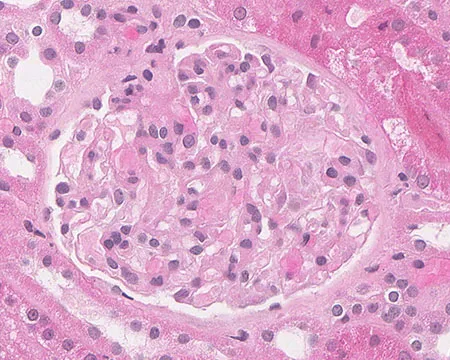

Proteinúria entre 0,5–1,0 g/dia na NIgA não é benigna e já se associa a maior risco de progressão renal. A evidência atual reforça <0,5 g/dia como alvo terapêutico, valorizando proteinúria cumulativa e tendência ao longo do tempo. Antes de pensar em imunossupressão, o foco deve ser otimização máxima da terapia de suporte e estratificação cuidadosa de risco.